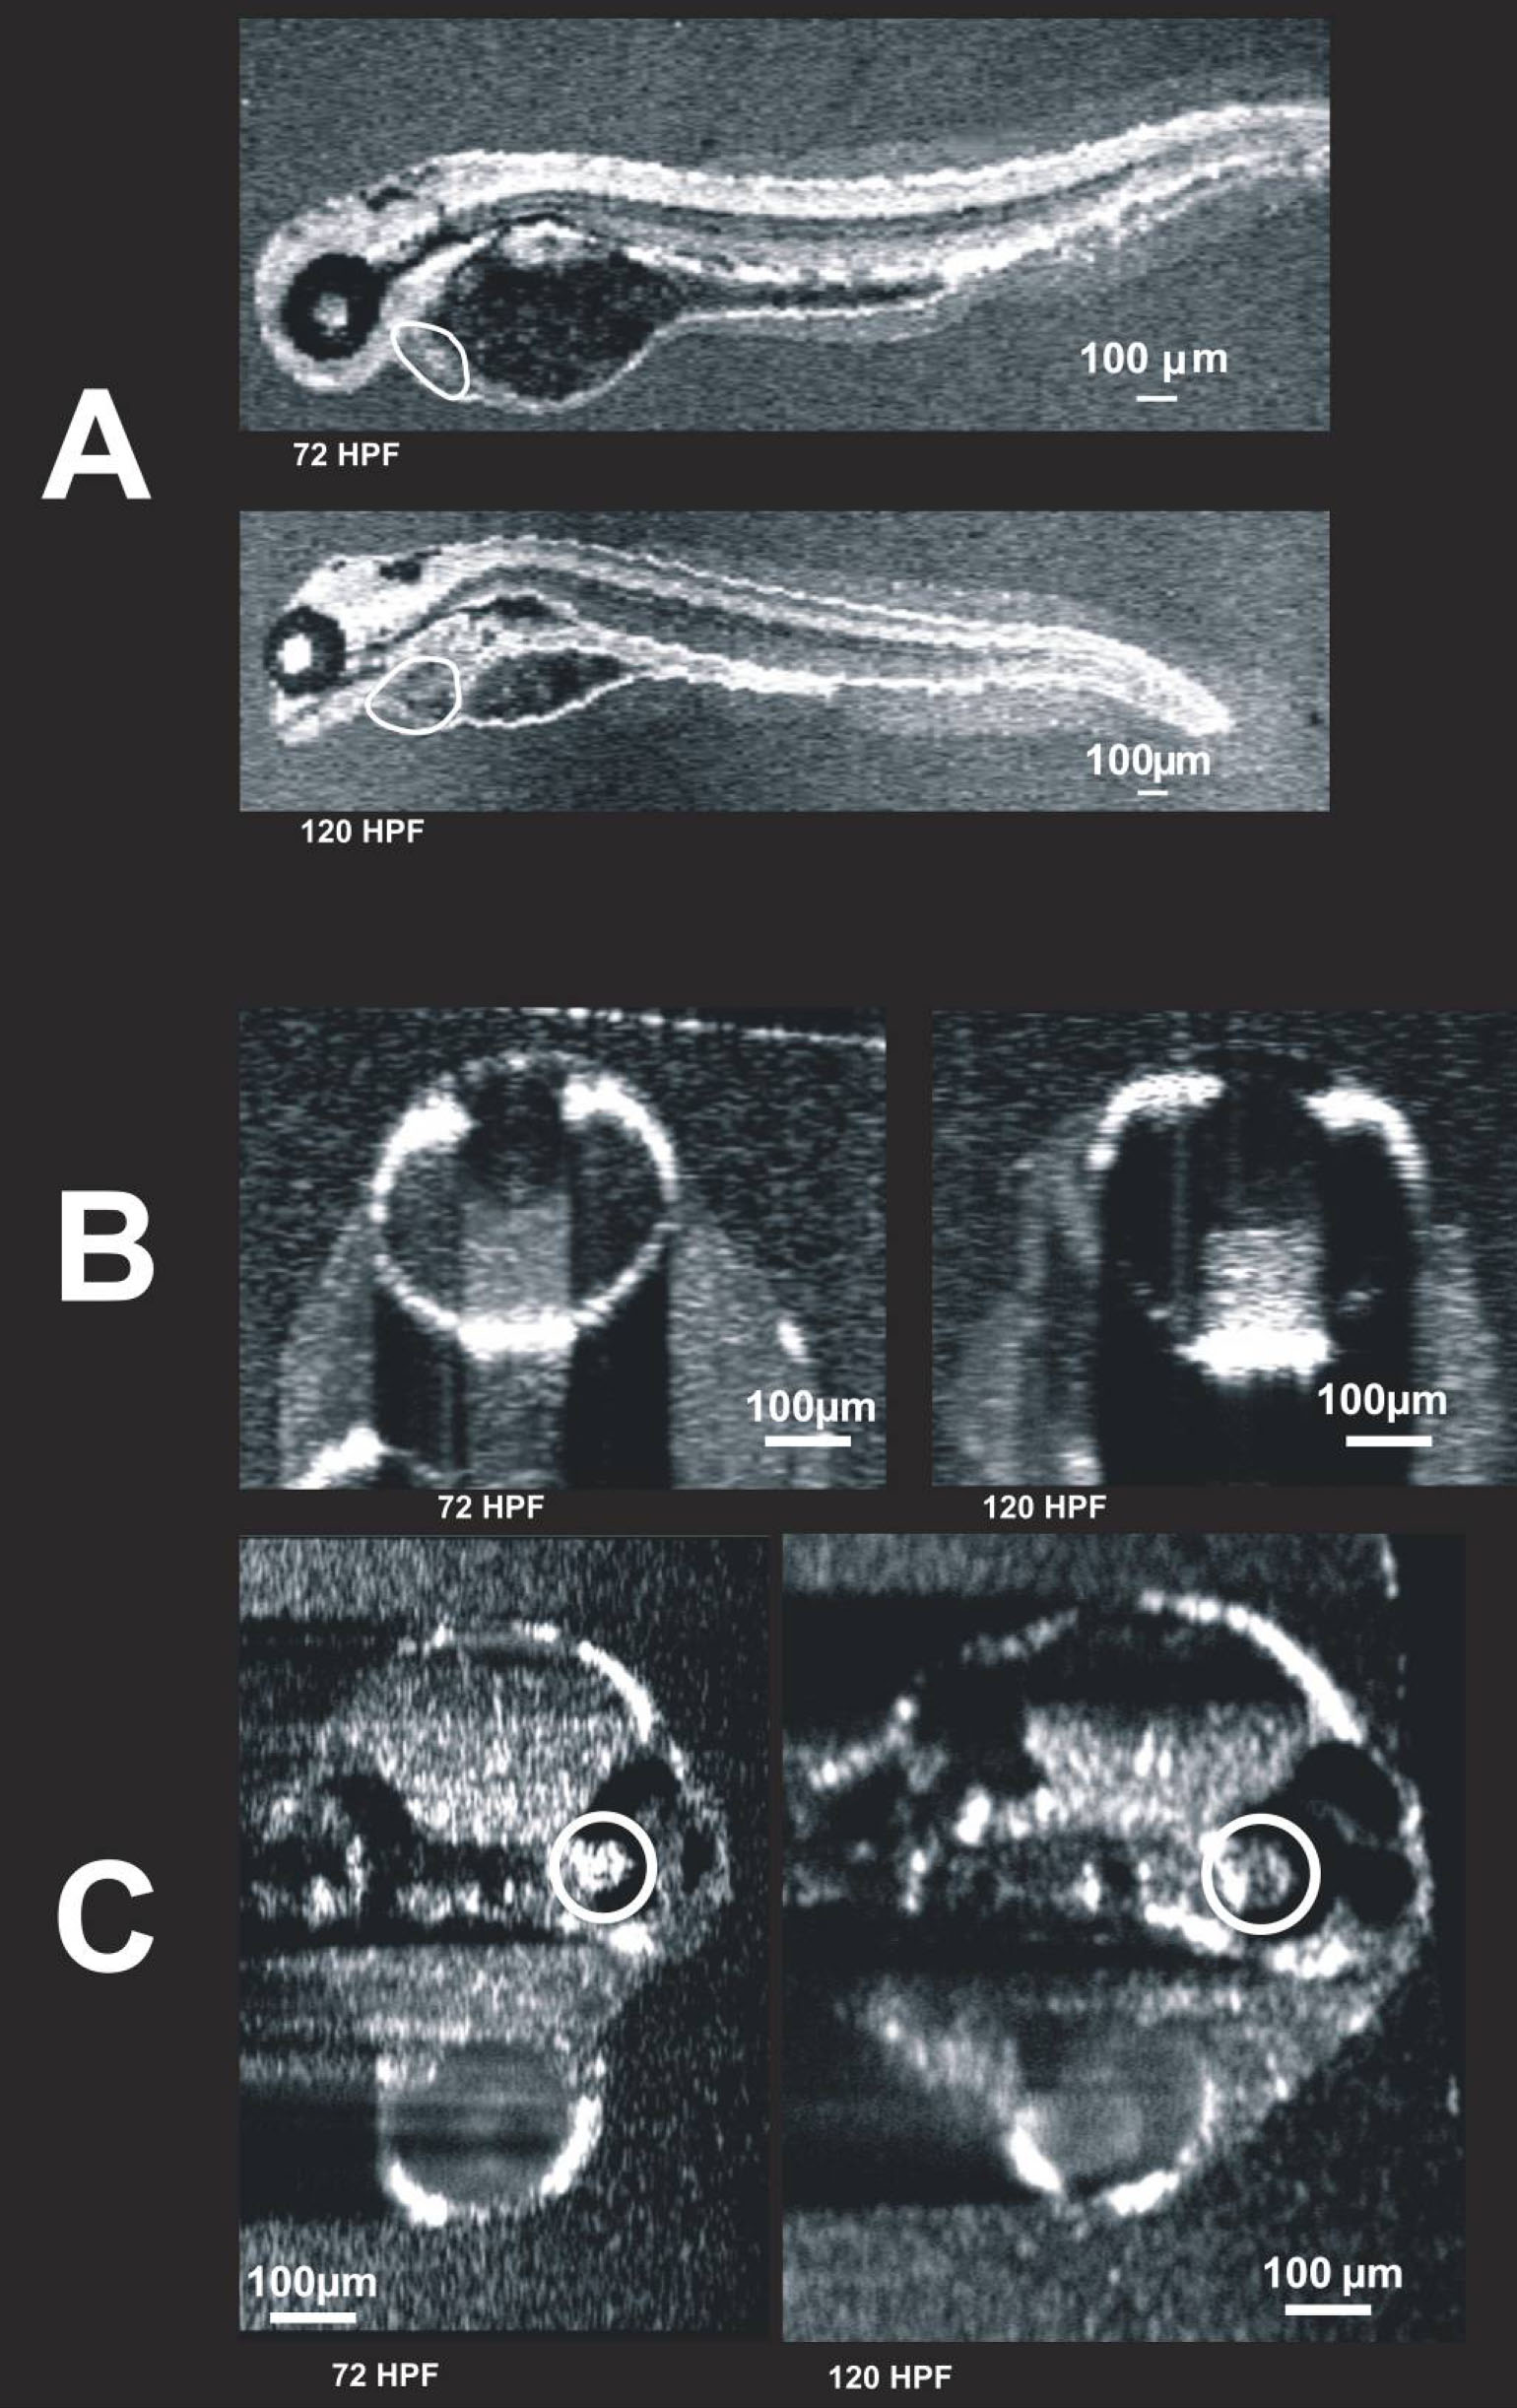

Figure 10 of Kagemann, Mol Vis 2008; 14:2157-2170.

Figure 10. Visualization of individual animals imaged on two different days. These images were obtained from the same embryo on two different days: 72 hpf and 120 hpf. C-mode images of the heart (A, circled), eye (B), and ear (C, circled) are presented. The heart is also visible in C, but blurred due to averaging over multiple cardiac cycles. It is possible that the first imaging session altered development. To compare the 120 hpf twice-imaged embryos to 120 hpf embryos imaged only once, refer to Figure 6 and Figure 9.